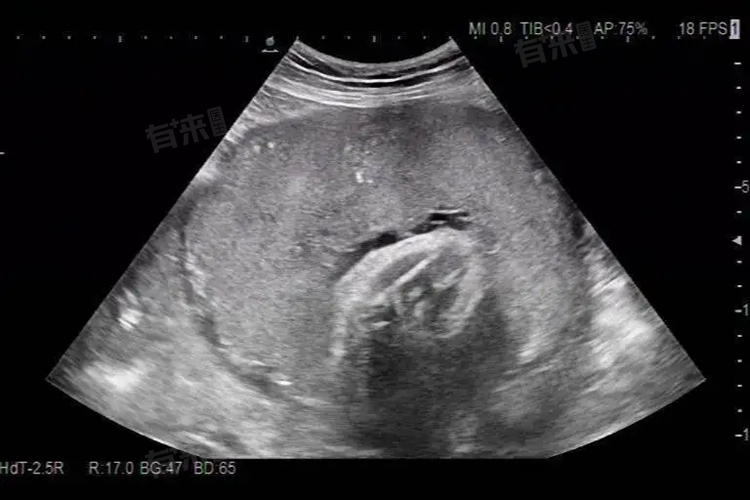

轮状胎盘是一种形态异常的胎盘,形态表现是胎盘的胎儿面中心内凹,周围环绕增厚,出现灰白色环。此种胎盘异常可能是由多种疾病或因素造成,常见因素包括胚胎着床位置异常、母体糖尿病等。